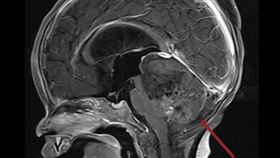

9月嬰腦腫瘤塞滿後顱窩!北醫這招救命

打破傳統放射治療年齡限制!一名才9個月大的小嬰兒,罹...